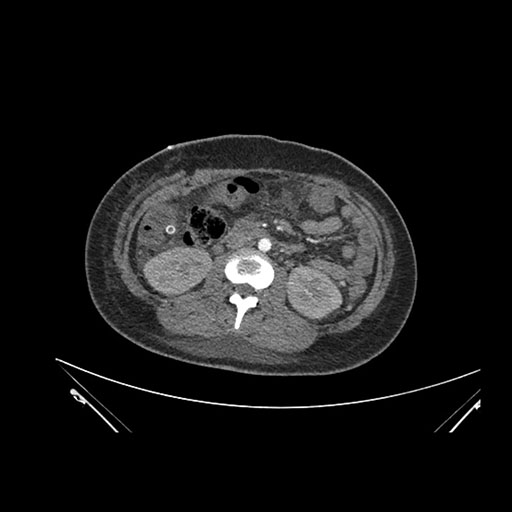

Imaging Analysis

Look through the patient's CT scan to identify any areas of concern for the necessary procedure.

Axial Venous

Based on initial findings, which issue(s) would you be most concerned about?